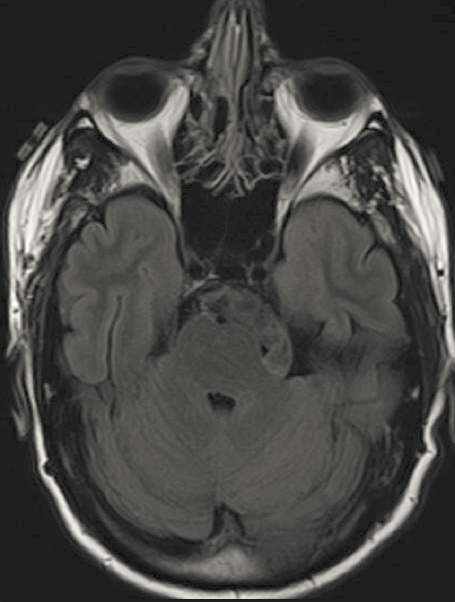

核磁共振图像

是利用核磁共振(nuclear magnetic resonance,简称NMR)原理,依据所释放的能量在物质内部不同结构环境中不同的衰减,通过外加梯度磁场检测所发射出的电磁波,即可得知构成这一物体原子核的位置和种类,据此可以绘制成物体内部的结构图像。

本图像来源翰·霍普金斯大学Elliot Fishman博士和Karen Horton博士的教学案例和图片。图像大小为455*600,8位灰度图像。为了增强本次实验效果,将此图像人为的进行了亮度调低。

亮度调低